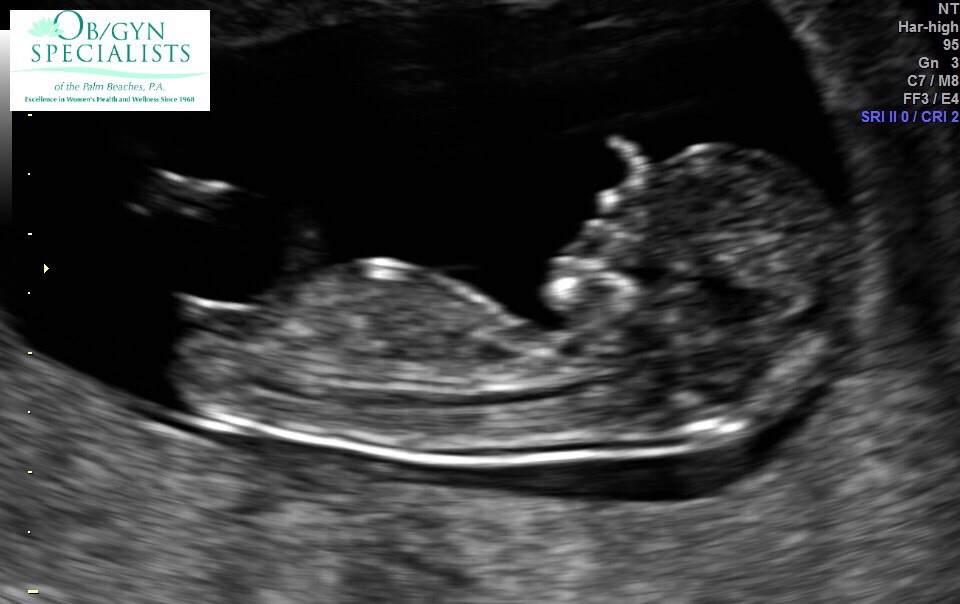

Got a surprise ultrasound today at 14w1d- thought we were just going to hear the heartbeat but we got pics too! Last time was at 9 weeks and she looked like a white smear on the U/S. Now look! So exciting!!